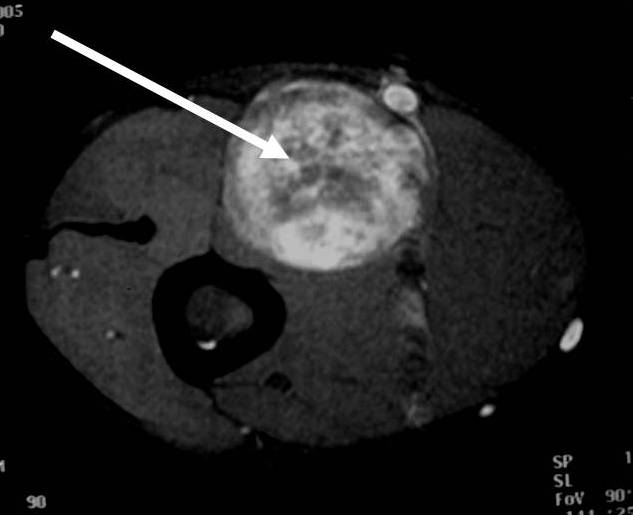

• T2: High signal (myxoid areas) with some heterogeneity (Fig. 3)

o Target Sign: Low signal central area (cellular/collagenous area; Antoni A) and high signal peripheral area (myxoid area; Antoni B)

Fig. 1-4 MR image demonstrates a 5 cm intermuscular mass in the anterior compartment of the arm arising along the course of the neurovascular structures. Isointense to muscle on T1W image and heterogeneous high signal on T2W with low signal in the central area (Antoni A) and peripheral high signal (Antoni B), known as “Target Sign”. Coronal image shows a structure entering and exiting the mass (median nerve).